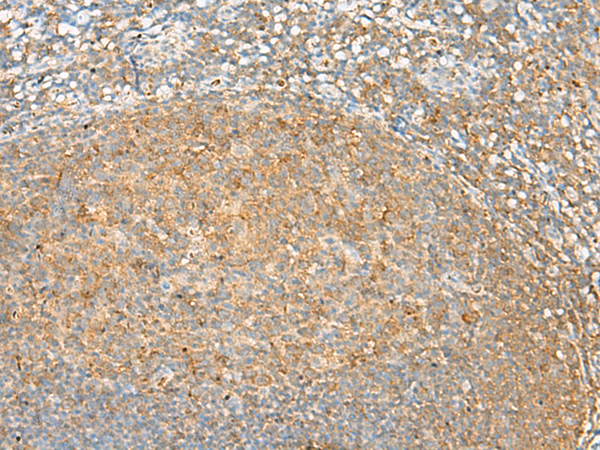

分类: 科研抗体货号: P13526别名: GIR; GPR72应用: IHC反应种属: Human, Mouse